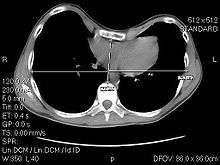

A CT scan showing a 3.58 index

The Haller index, created in 1987 by Dr. Haller, Dr. Kramer, and Dr. Lietman,[1] is a mathematical relationship that exists in a human chest section observed with a CT scan. It is defined as the ratio of the transverse diameter (the horizontal distance of the inside of the ribcage) and the anteroposterior diameter (the shortest distance between the vertebrae and sternum).[2] It is of diagnostic use in vivo.

A normal Haller index should be about 2.5. Chest wall deformities such as pectus excavatum can cause the sternum to invert, thus increasing the index, which can reach 3.25 or even as high as 5.5[3][4]